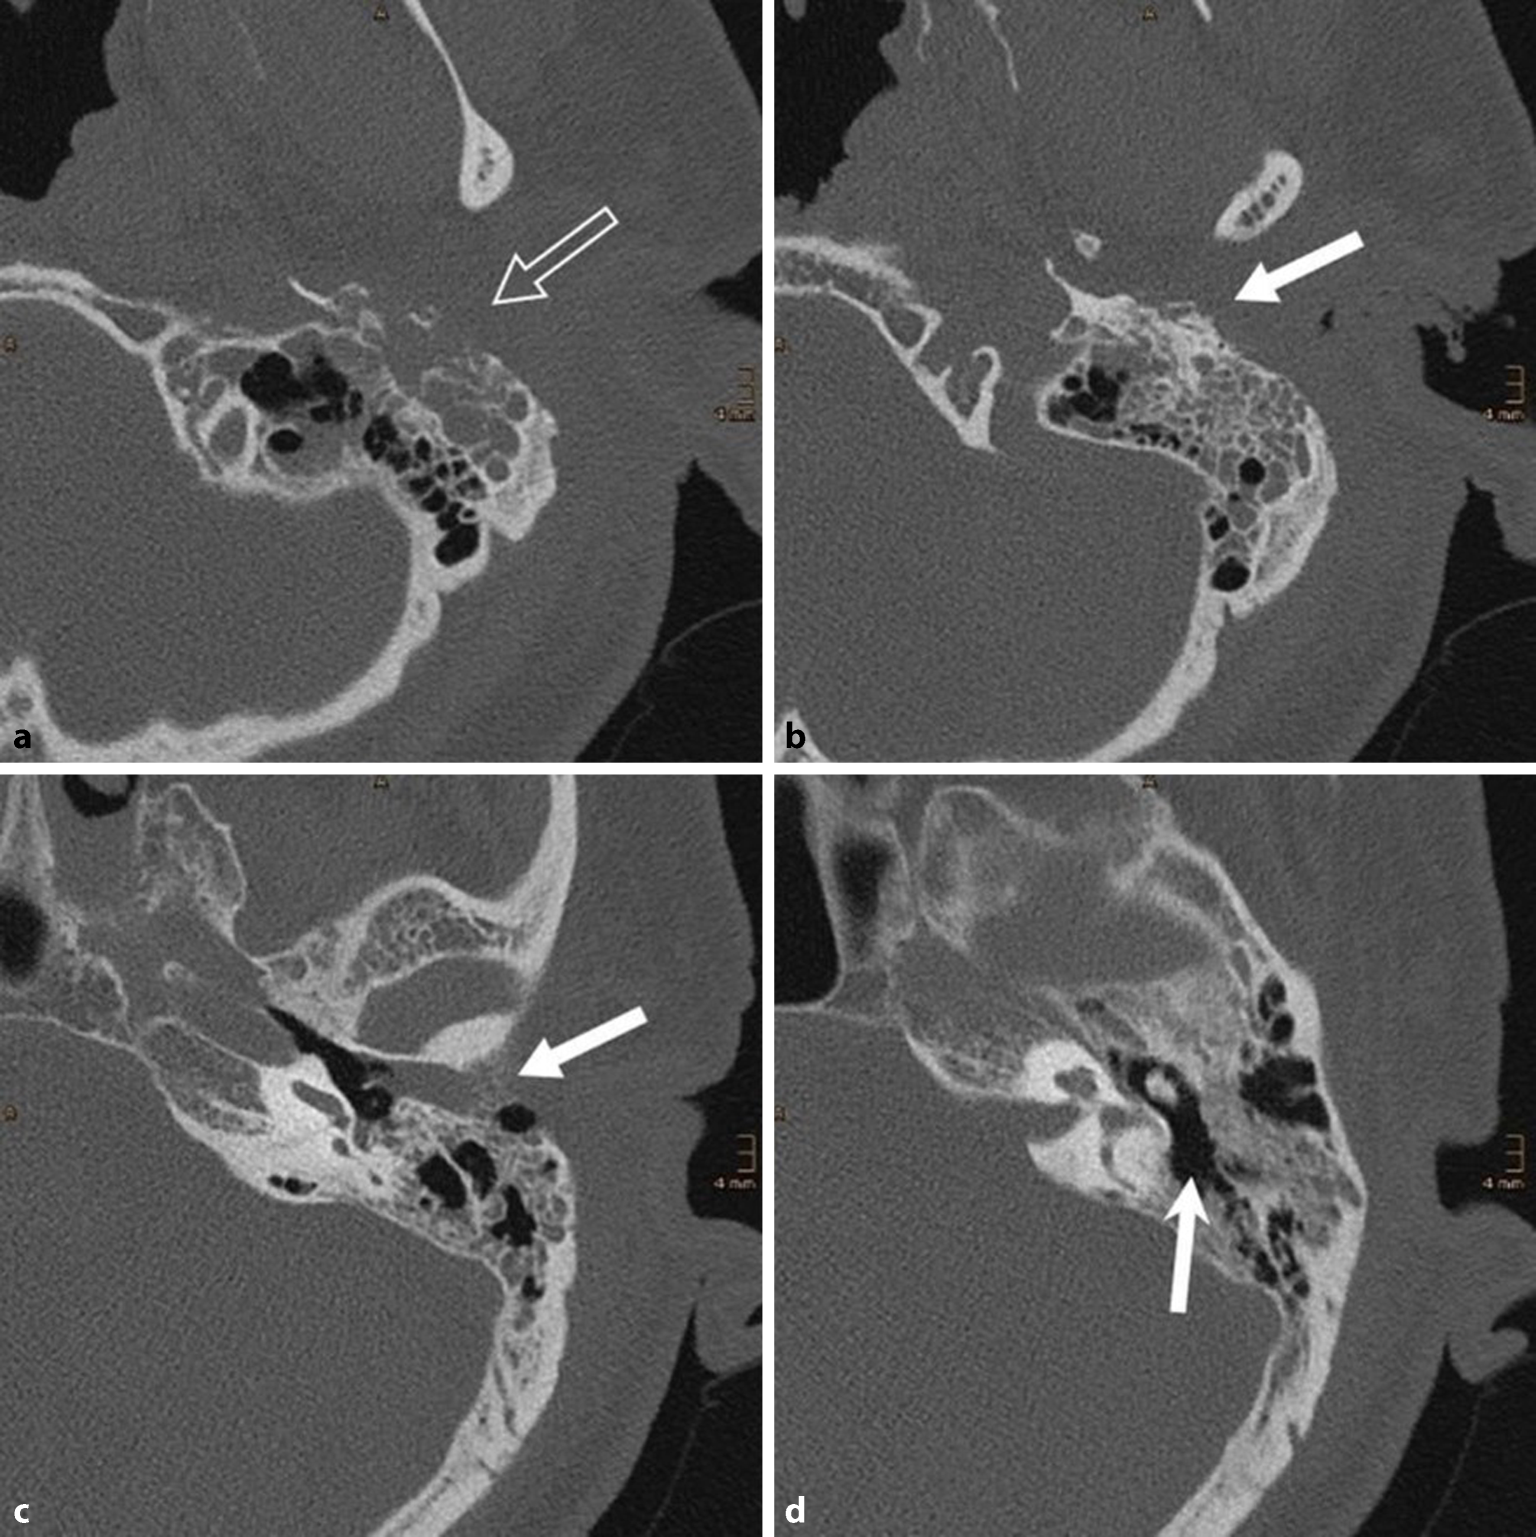

Abb. 4

Bild eines Plattenepithelkarzinoms des äußeren Gehörgangs. Aufgrund der klinischen Ähnlichkeit zur Otitis externa necroticans (OEN) bei unklarer Befundkonstellation frühzeitige Gewebeprobe zur histopathologischen Abklärung empfohlen

Die seltene Differenzialdiagnose des Gehörgangskarzinoms sollte bei jedem Fall einer OEN mitbedacht werden und bei potenziellem Verdacht eine Biopsie zur histopathologischen Aufarbeitung entnommen werden (Abb. 4; [11]). Eine weitere Differenzialdiagnose stellt das Gehörgangscholesteatom dar (Abb. 5). Hier kommt es typischerweise zu einer von festen Krusten bedeckten Aushöhlung im Bereich des Gehörgangsbodens mit freiliegendem Knochen. Eine sichere Abgrenzung zur OEN erfordert bildgebende Verfahren, anhand derer eine Ausbreitung der Entzündung über die Grenzen des Gehörgangs hinaus ausgeschlossen werden kann.